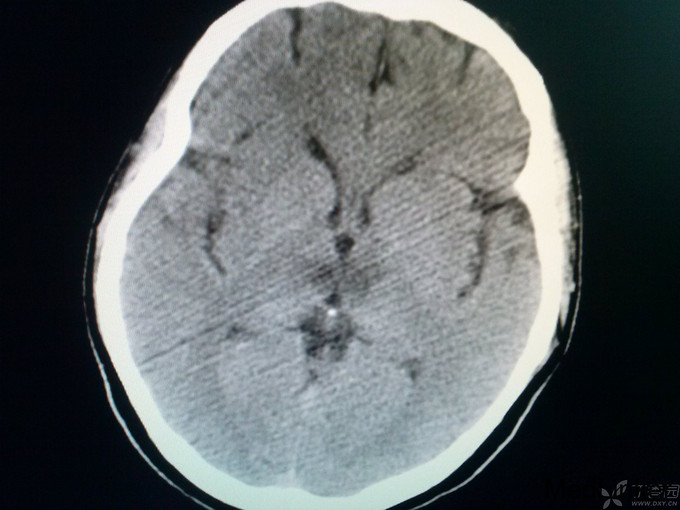

查体:体温36.0℃,脉搏60次/分,呼吸20次/分,血压120/80mmHg。平车推入病房,查体不合作。皮肤巩膜无黄染,胸前见手术瘢痕,双肺呼吸音粗,未闻及罗音,心室率72次/分,律绝对不齐,无病理性杂音,腹部膨隆,膀胱区叩诊为浊音,肝脾肋下未触及。神经系统专科查体:嗜睡,双瞳孔同大同圆,双眼直径3.0mm,对光反射灵敏,双侧鼻唇沟对称,咽反射(+),四肢对疼痛刺激有反应,肌张力正常,肱二头肌、肱三头肌肌腱及膝反射、跟腱反射均亢进,病理征:Babinski征L(+),R(+),颈无抵抗,Kernig征(-)。头CT:未见异常;入院后给予甘露醇125毫升间隔12小时静点一次,呋塞米20毫克间隔12小时静点一次。给予华法林2.5mg日一次口服、奥扎格雷80mg日一次静滴、活血化瘀、营养神经治疗。如是您是首诊患者,有何不同治疗方案?双抗+华法林、稳定斑块合适吗?理由呢? 4月27日: 患者嗜睡,叫醒后,问话能正确回答,患者不能识别物体的形状,左右肢体能识别,查体:嗜睡,双瞳孔同大同圆,双眼直径3.0m,对光反射灵敏,双侧鼻唇沟对称,咽反射(+),四肢活动可,肌张力正常,肱二头肌、肱三头肌肌腱及膝反射、跟腱反射均亢进,病理征:Babinski征L(+),R(+),颈无抵抗,Kernig征(-)。今日复查头CT:后续提供。同时华法林改为3.75mg日一次口服。病灶进展?还是? 4月28日 患者嗜睡,叫醒后,患者左右肢体失认,失算,尿量尚可,心电监护示:血压:96/70mmHg,心率140次/分,律不齐,血氧饱和度99%,现查体:嗜睡,呼吸平稳,肢体疼痛刺激可动,双瞳孔直径3.0mm,对光反射灵敏,双巴氏征(+)。双下肢无浮肿。给予低分子肝素4100单位间隔12小时皮下注射,患者心室率快,给予西地兰0.2mg静推。病灶进展?还是? 5月1日 患者处于嗜睡状态,但嗜睡时间较前明显缩短,问话可答,但答非所问,看似条理清晰,实则“子无须有”,呈现“虚构现象”,如问“几个孩子”,说“1个”,“男孩还是女孩”,答曰“男孩”,实则没有;问“什么水果”,有时能答对,绝大多数回答错误;但患者说话声调低、音量小,复述正常,心电监护示:血压107/77mmHg,心率89次/分,SPO2:98%,查体:嗜睡状态,丘脑性失语,无面瘫,双瞳孔直径3.0mm,对光反射灵敏,双眼上视、下视受限,以下视明显,四肢肌力5级,肌张力正常,双巴氏征(+)。 4月29日CT:

诊断: 1.BVTS 2.风心病,瓣膜置换术后 3.房颤